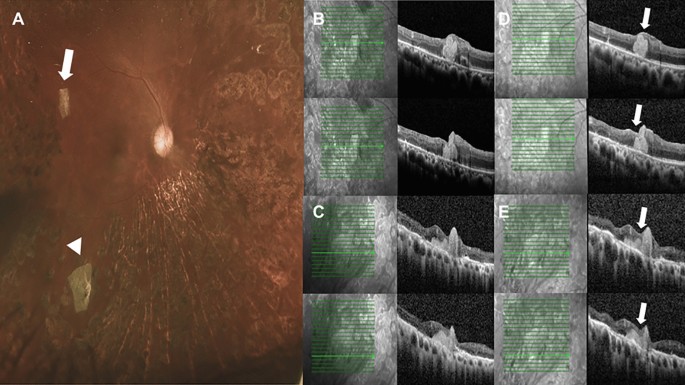

Postoperative color fundus photograph and serial optical coherence tomography (OCT) exams of case 1. (A) Color fundus photograph showed the two retinal breaks sealed securely by two human amniotic membrane (hAM) grafts (arrow and arrow head). (B,C) Two months after surgery, OCT scans over the location of superior temporal break (arrow) and inferior temporal break (arrow head) showed the retina breaks well sealed by the grafts. (D,E) One year later, OCT scan over the same location showed that the grafts stayed in place without graft dislocation or lysis. Besides, some retina and glial tissue regeneration were observed at the retina break edges(arrows).

For patients in the hAM group, eight cases had TRD with retinal breaks made during membrane delamination. Two cases had preoperative CTRRD. Table 2 shows the demographic data of the patients. Five eyes received silicone oil endotamponade, two eyes had 24% SF6 infusion, two eyes had 13% C3F8 infusion, and one eye had room air infusion. The mean follow-up duration was 6.78 months. Postoperatively, the retina was successfully reattached in all of the eyes. For five eyes with silicone oil tamponade, silicone oil was removed smoothly without recurrence after an average of 4.4 months. Fundus examinations, fundus photography, and serial OCT confirmed that the retinal breaks had been sealed by hAM grafts. Serial OCT revealed that all the hAM grafts stayed in place without dislocation. The graft size also seemed to be stationary without lysis. Moreover, from OCT, partial tissue regeneration was also observed over the retinal breaks (Fig. 1). In another patient (Fig. 2, case 7), the tissue regeneration effect was even more marked with the large retinal break all covered by regenerated glial and possible retinal tissue along the surface of the hAM graft. No postoperative major adverse event was found. An accident happened in one patient (Fig. 2D,E, case7); the break was too large, and the first hAM graft dislocated into the subretinal space during manipulation; thus, the second piece of the hAM was implanted, and the graft was positioned well into place under perfluorocarbon liquid. Postoperatively, the displaced subretinal hAM plug did not cause inflammation or retinal atrophy during serial postoperative OCT scans. Surprisingly, from the OCT, the partial recovery of the ellipsoid zone of the originally detached retina was observed.